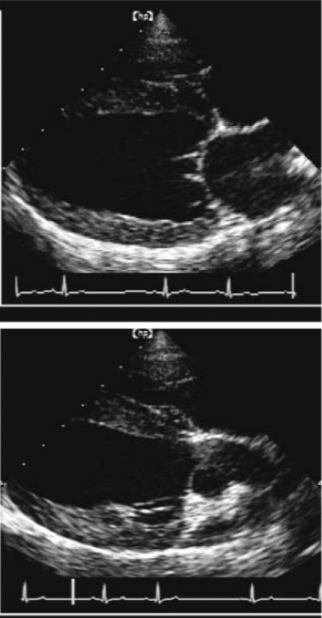

Name the ECHO VIEW and STRUCTURES

LEFT APICAL VIEWS